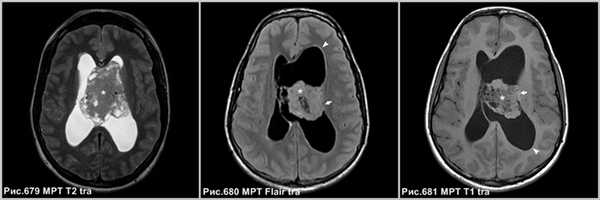

Центральная нейроцитома в виде неоднородной структуры объёмного образования, расположенного в боковом желудочке, связанное с прозрачной перегородкой (звёздочки на рис.679-681), сопровождающееся расширением бокового желудочка (головки стрелок на рис.680, 681). МРТ демонстрирует врастание опухоли в стенку бокового желудочка левого полушария большого мозга (стрелки на рис.680, 681).

Контрастное усиление

Накопление контраста средней выраженности, может быть минимальным и, даже, отсутствовать.

На МРТ в режиме Т1 после контрастного усиления определяется неоднородное накопление контраста в солидных участках опухоли (головки стрелок на рис.682-684). В области внутриопухолевых кист усиление отсутствует.